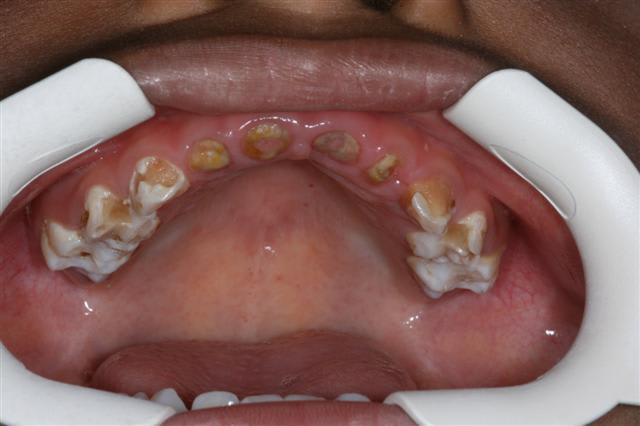

malheureusement ce n'est pas fait et qd ils arrivent à 3 ans ils st comme la photo jointe

Pour Ploc : je ne parlais pas de cas dramatiques comme celui que tu as présenté. Naturellement, cela sort du cadre de l'entretien courant.

pr marc,ce n'est pas un cas dramatique c'est mon quotidien du jeudi:)